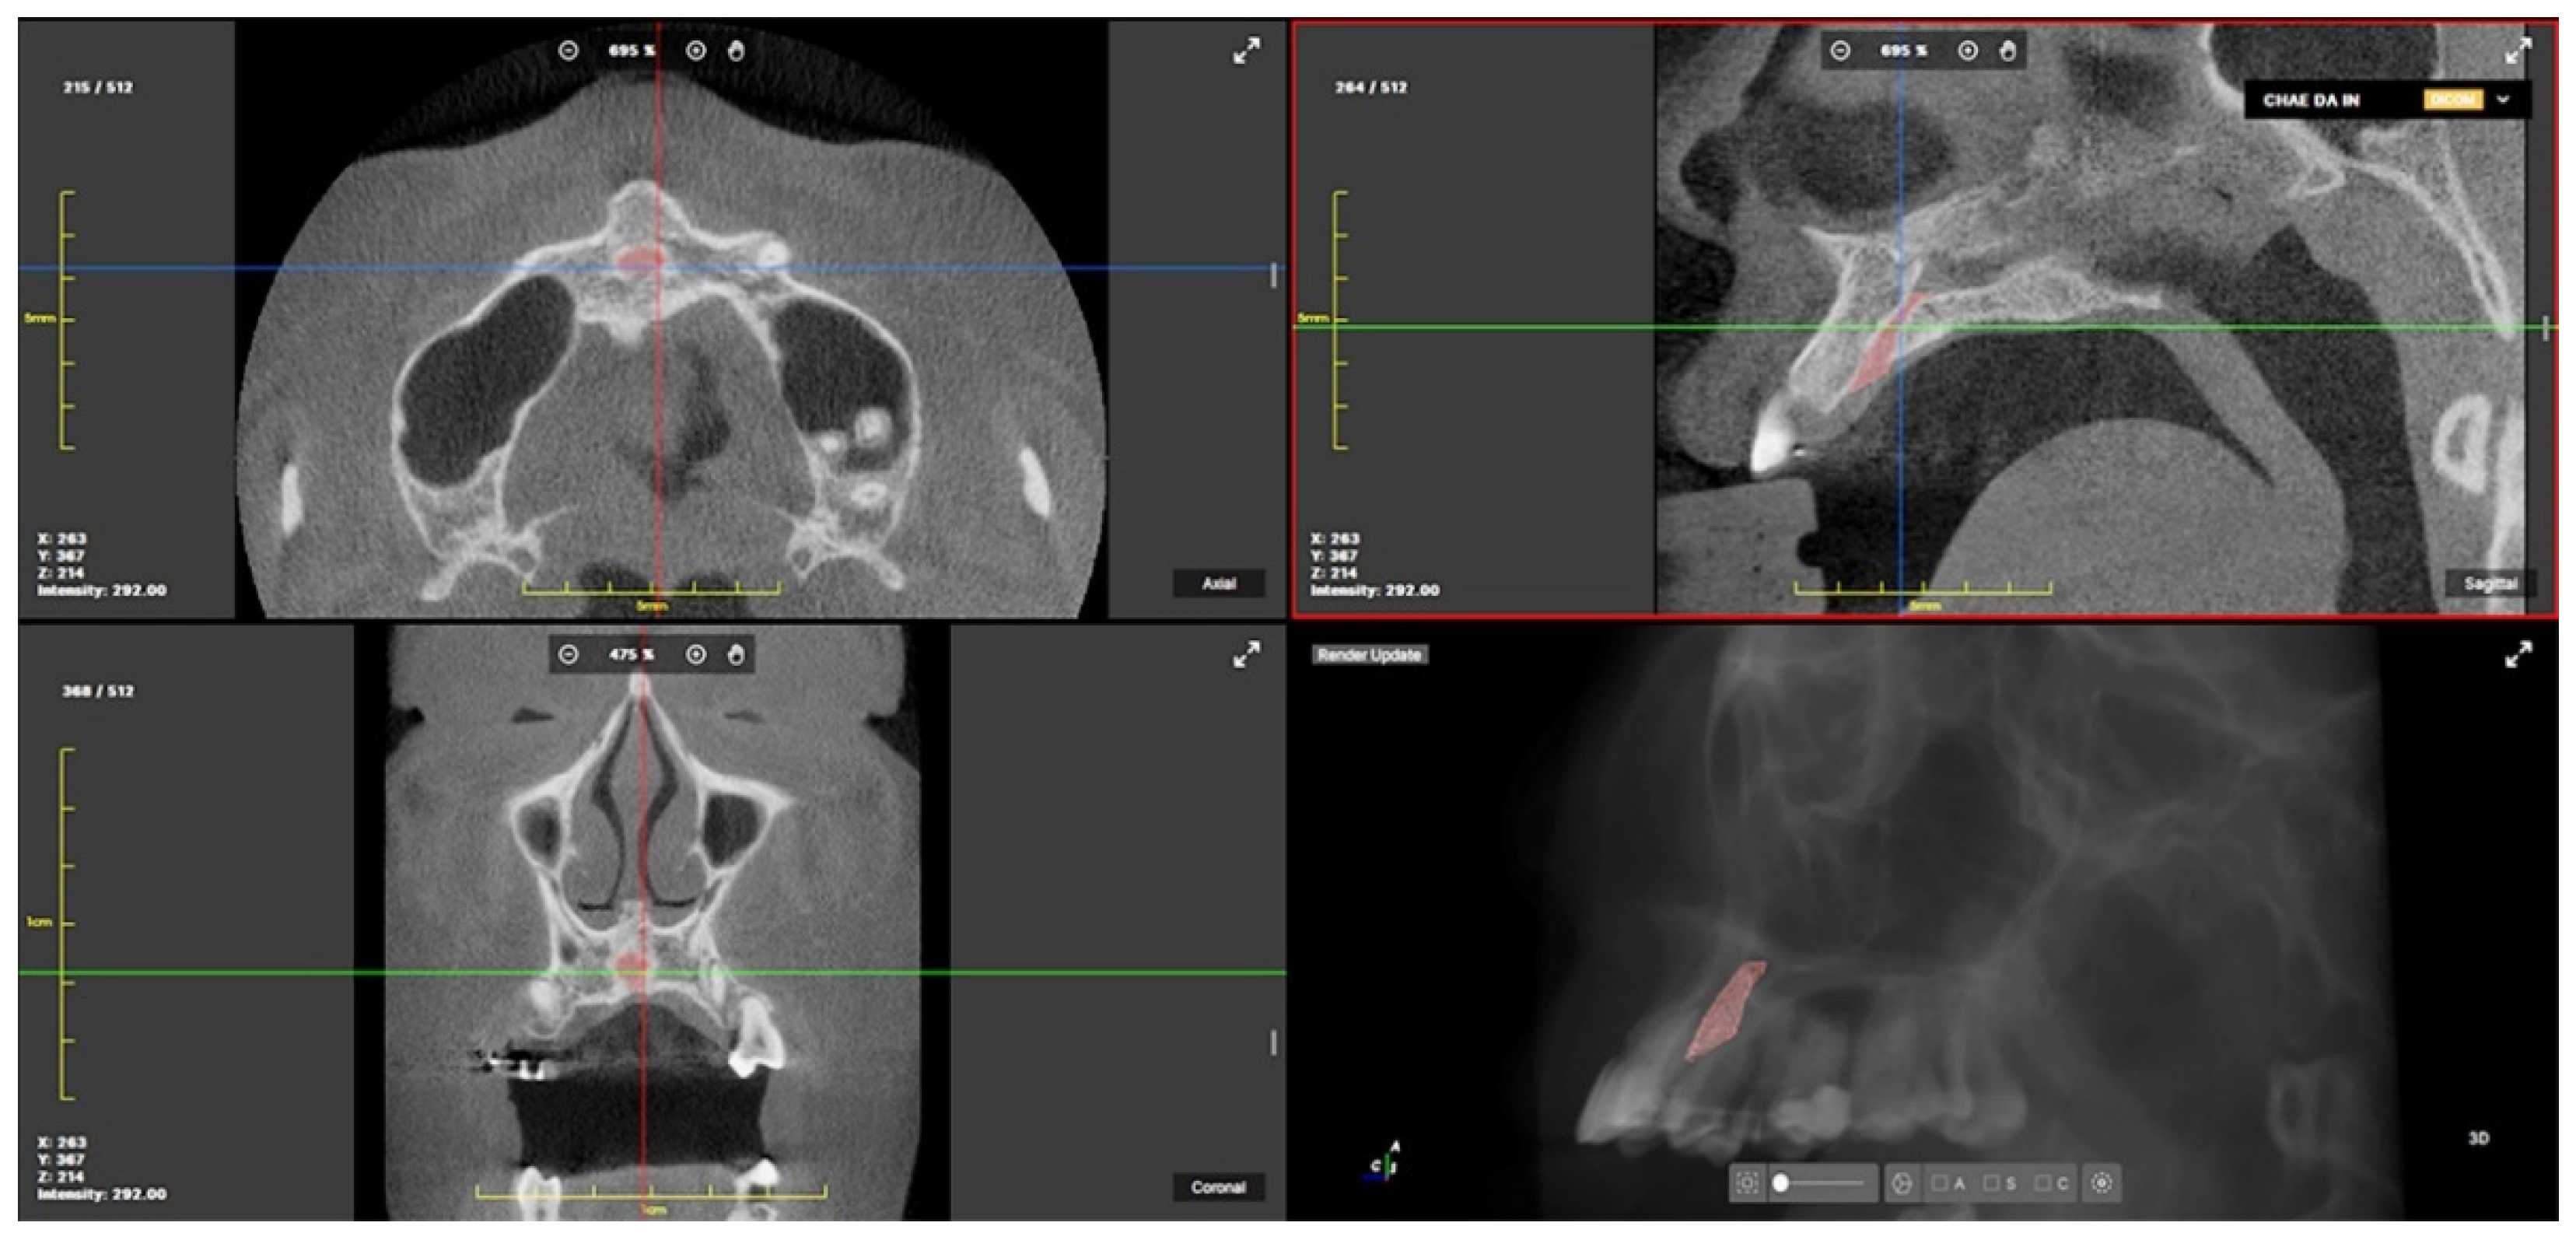

2.3. CBCT Landmarks, Reference Planes and Measurements

| Measurement | Definition |

|---|---|

| #11Rm-#21Rm | Mediolateral distance between #11Rm and #21Rm (mm) |

| #11Rm-Cat | Anteroposterior distance between #11Rm and anterior margin of IC (mm) |

| #21Rm-Cat | Anteroposterior distance between #21Rm and anterior margin of IC (mm) |

| IC LP width | Labiopalatal width of IC (mm) |

| IC ML width | Mediolateral width of IC (mm) |

| #11Rt-#21Rt | Mediolateral distance between root apices of #11 and #21 (mm) |

| #11Cr-#21Cr | Mediolateral distance between crown tips of #11 and #21 (mm) |

| IC volume | Volume of IC from oral opening to nasal bifurcation (px, cm3) |